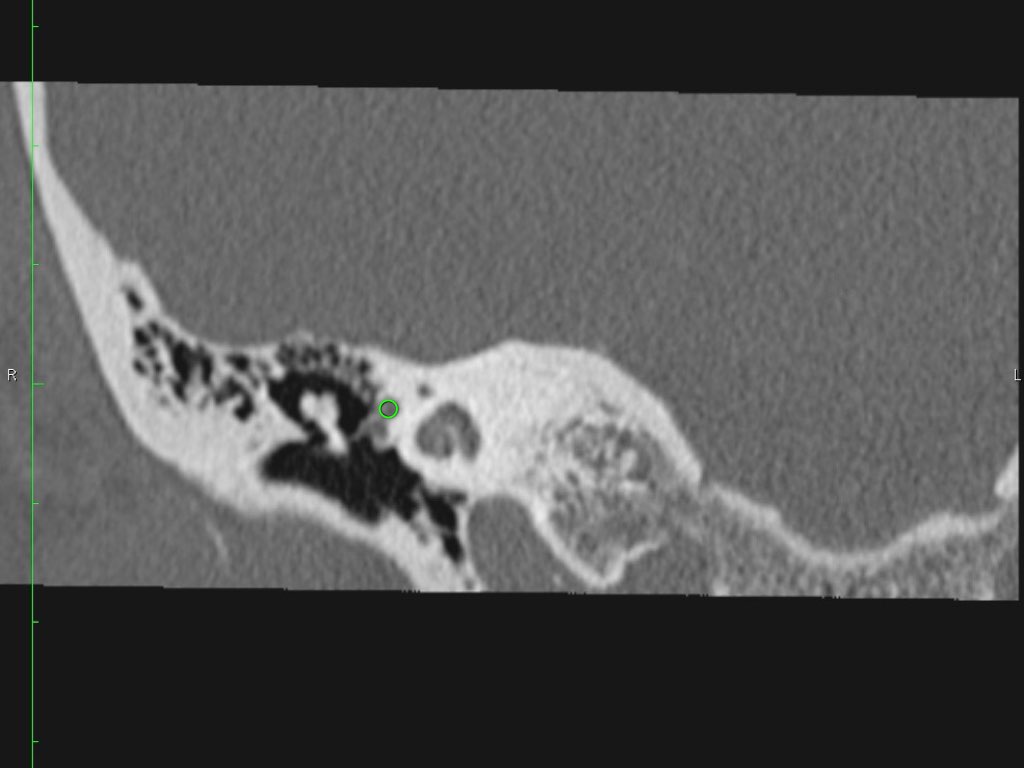

Có một khối mô mềm ở vùng thượng nhĩ.

Lưu ý hình ảnh thủng màng nhĩ (mũi tên vàng) và bào mòn ống bán khuyên ngoài (mũi tên đỏ).

Scutum bị tù mòn.

Đây thường là cấu trúc xương đầu tiên bị bào mòn do cholesteatoma, hình thành bởi sự co kéo vào trong của pars flaccida màng nhĩ vào vùng thượng nhĩ.

Nếu quá trình co kéo tiếp tục tiến triển sẽ dẫn đến phá hủy chuỗi xương con.

Nếu cholesteatoma lan ra phía sau qua aditus ad antrum vào trong xương chũm, có thể gây bào mòn tegmen mastoideum làm lộ màng cứng, đồng thời bào mòn ống bán khuyên ngoài dẫn đến điếc và chóng mặt.